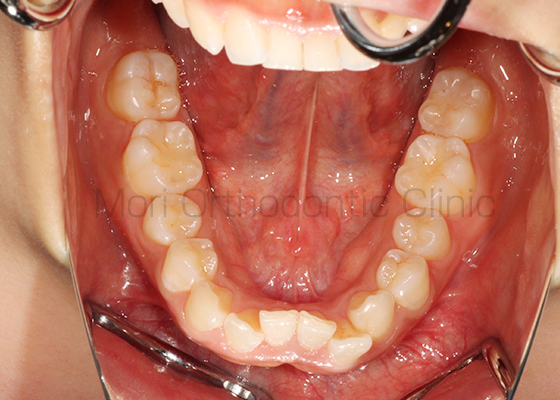

術前

術後

| 主訴 | 出っ歯、歯並びが悪い |

|---|---|

| 診断名 | AngleⅠ級叢生 |

| 年齢 | 21歳11か月 |

| 治療装置 | Multi-Bracket(フルリンガル) |

| 抜歯部位 | 14,24,34,44 |

| 治療期間 | 2年7か月 |

| 治療費 | 1,180,200円(税込) |

| リスク・副作用 | 矯正治療による歯の移動に伴う痛み、歯根吸収、歯肉退縮、虫歯 |